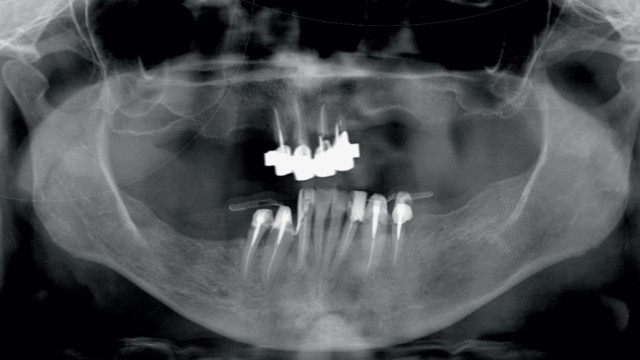

Radiografia pre-operatoria che evidenzia la presenza di elementi dentari con plurime ricostruzioni che presentano infiltrazioni cariose oltre ad importanti problemi parodontali.